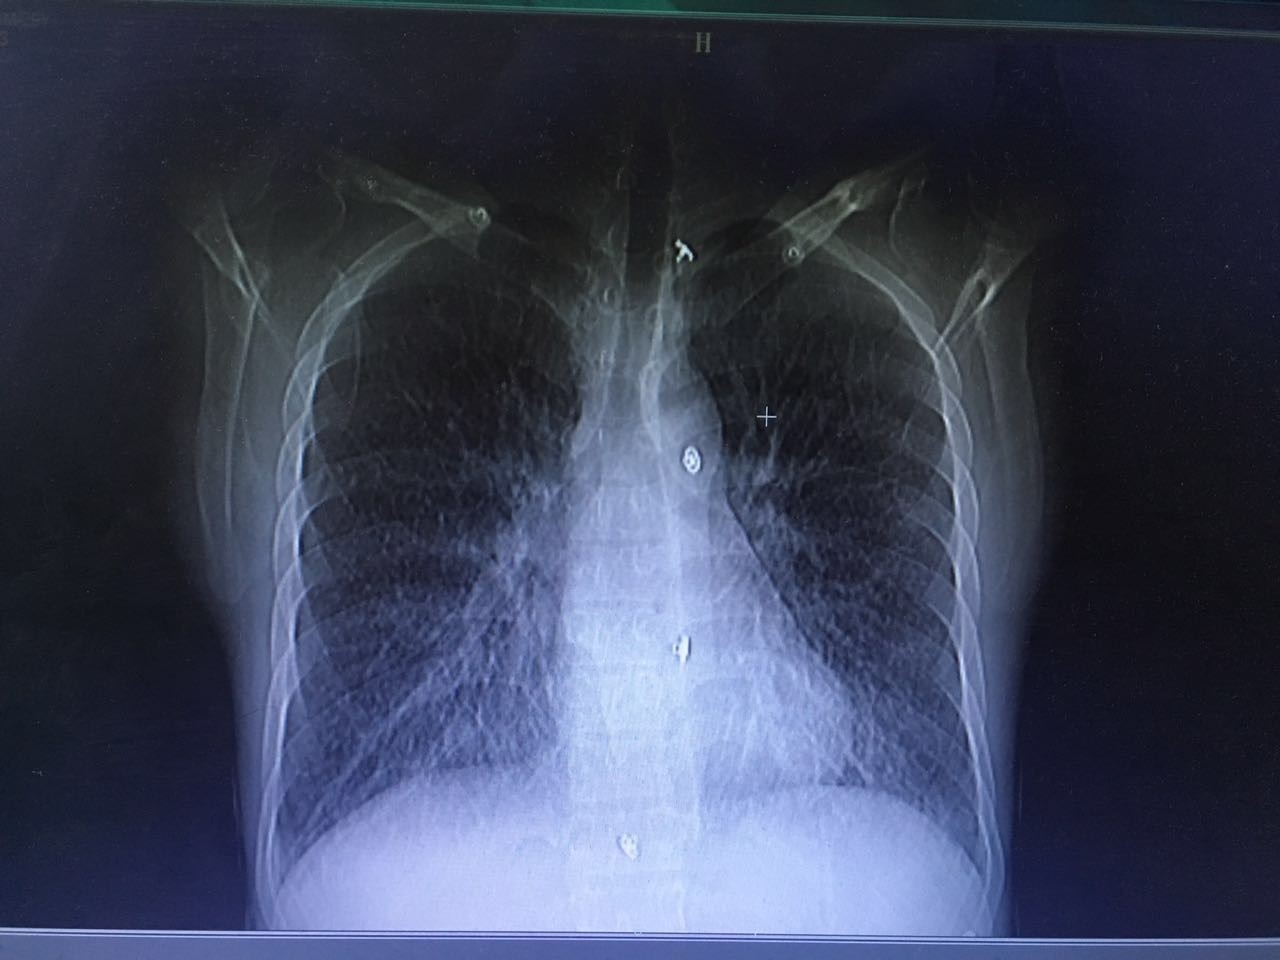

第二天,肺部CT做下来,我们傻了,和胸片差别太大了!从中下肺开始,那是大片的阴影啊!CT提示为间质性肺炎,找放射科主任读片,认为不符合肺结核、肺癌的表现(图1-3.)马上再回到病床前再次确认——没有吸烟史、没有慢性咳嗽史、没有咯血、没有盗汗史。再查体:浅表淋巴结确实不肿大,双肺呼吸音可以算略粗糙也可以算清晰。——这么这么静默的肺部体征,这么这么差的影像学结果,马上补查肿瘤标志物和自身免疫全套吧!

图1